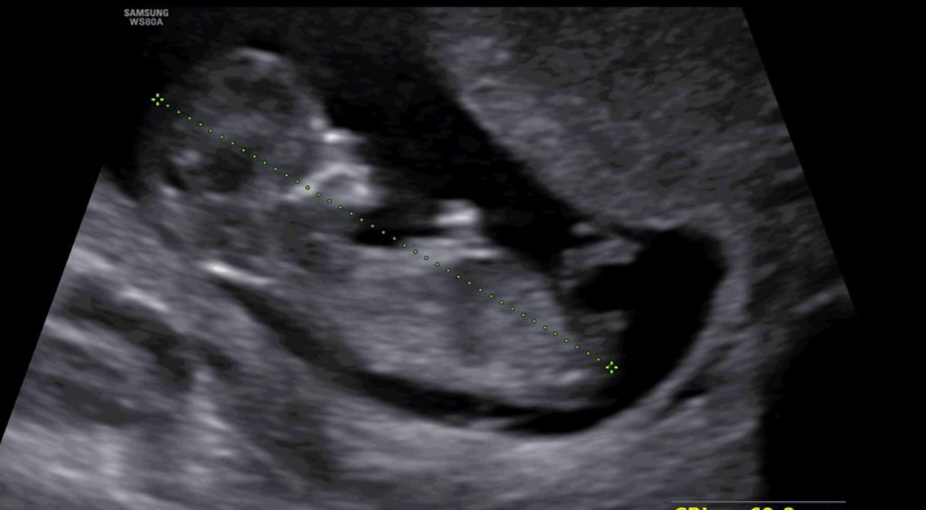

zariiii7070 مدیر استارتر عضویت: 1403/02/22 تعداد پست: 190 سر دختر یکم طعم دهن عوض میشه انگار تلخه و اینکه معده درد میگیره یا میترشه انگار وبکم دل درد میگیره عکس سونو گذاشتم ببینین

کافرمؤمن عضویت: 1403/02/03 تعداد پست: 3792 این عکس سونو اخی جانمن اینارو بلد نیستم🤭 فقط 20 هفته و 6 روز به تولد باقی مونده ! 1 5 10 15 20 25 30 35 40 در من کافریست که به تو سخت ایمان دارد خدا♥️✨